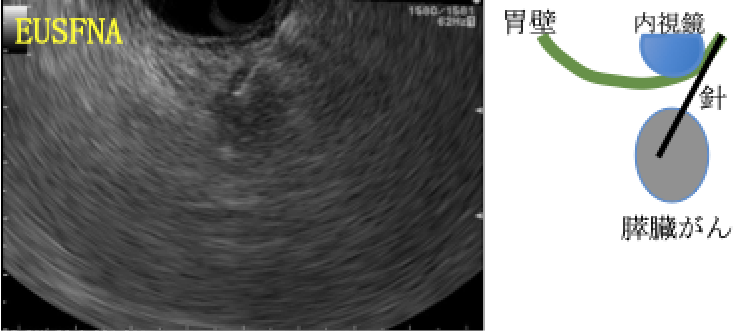

※⑦ 超音波内視鏡下吸引生検・細胞診(EUSFNA)

超音波内視鏡でがんを確認し、胃内や十二指腸内から細い針を穿刺し、がんの細胞を採取する検査です。がんを確認することができれば診断能の高い検査です。検査によって出血・膵炎などを合併する可能性があるためEUSFNAを受ける際は入院が必要です。極めて稀に胃壁などの穿刺した場所で膵臓がん細胞が発育することがあります(穿刺ルート播種)。